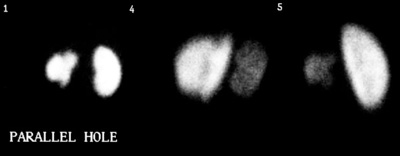

Acute Rejection: Tc-MAG3 renal scan in a post-transplant patient. Flow and functional images, and renal curves are shown from a baseline post-op scan and a scan performed at 5 weeks post transplant. Baseline exam demonstrates prompt perfusion to the transplant. The 5 week post-op examination demonstrates markedly decreased renal perfusion to the transplanted kidney compared to baseline which is characteristic of acute rejection. The kidney to aorta flow ratio has decreased from 0.52 to 0.16 (See curves below). |

Acute Rejection: Tc-MAG3 renal scan functional images from the same case demonstrate essentially normal function on the baseline exam, but prolonged cortical retention and no evidence of excretion of the tracer on the 5 week examination. |

Acute Rejection: Tc-MAG3 renal scan curves from the same patient confirm visual findings of decreased perfusion and renal function in this patient with acute transplant rejection. |